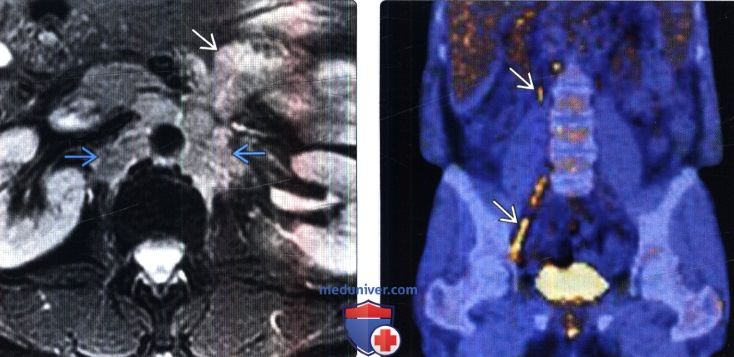

КТ ретроперитонеального фиброза: Изображения и диагностика

Раздел: Мудрость в деталях